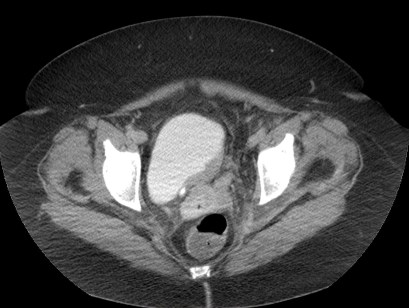

En series de estudio se ha estimado una sensibilidad, especificidad, VPP y VPN del 93%, 99%, 98% y 97% respectivamente. Se realiza añadiendo cortes finos, con una fase excretora, una buena hidratación del paciente y con el uso de diuréticos para conseguir una buena dilatación de la vejiga y una adecuada opacifiación de la misma.

Se debe jugar con las ventanas, usar amplias y estrechas , con el fin de maximizar la búsqueda de defectos de repleción. Se debería incluir el estudio de imágenes en axial y coronal, ya que algunas lesiones son más evidentes en una orientación que en otra.

- Masas focales y Defectos de repleción.

El engrosamiento difuso de la vejiga suele deberse a entidades benignas como la cistitis, obstucción o vejiga neurógena; muy raramente corresponden a cáncer.

Los tumores < 1 cm pueden pasar desapercibidos, por que el uso de una urografía TC no debe excluir la necesidad de realizar una cistoscopia en pacientes con hematuria y alto riesgo.

- Realce temprano por TC con contraste y cortes finos: algunos autores defienden que también habría que examinar la vejiga mediante la obtención de imágenes en una fase previa (60 -80 seg.) tras la inyección de contraste ya que el cáncer de vejiga muestra un realce precoz que es mayor que el de la pared vesical normal. Además de la fase excretora, esta fase precoz es una herrmienta útil que podemos usar, si bien no de manera sistemática, por lo menos ante determinados casos según cuando el riesgo clínico es elevado o tenemos hallazgos en otras pruebas, como una ecografía, los cuales podríamos analizar de una manera más dirigida.